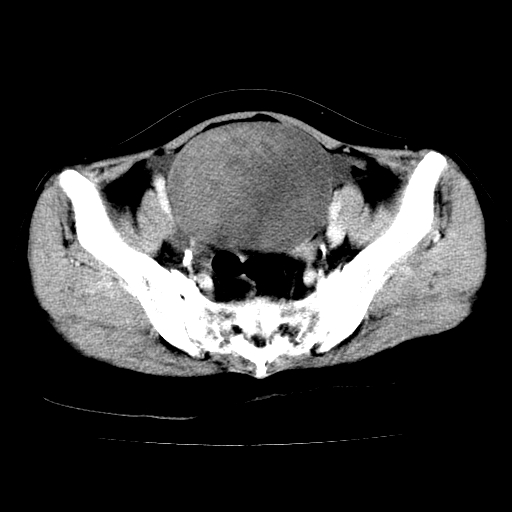

标题: CT24785:女,62岁,发现下腹部肿物半年。 [打印本页]

标题: CT24785:女,62岁,发现下腹部肿物半年。

女,62岁,发现下腹部肿物半年,下腹部不适。

老年女性患者,盆腔囊实性占位,ct增强不均匀强化,未见壁结节,未见腹水及盆腔积液,考虑附件囊腺瘤可能性大!

实性成分太多,要是囊腺瘤也要考虑恶性。